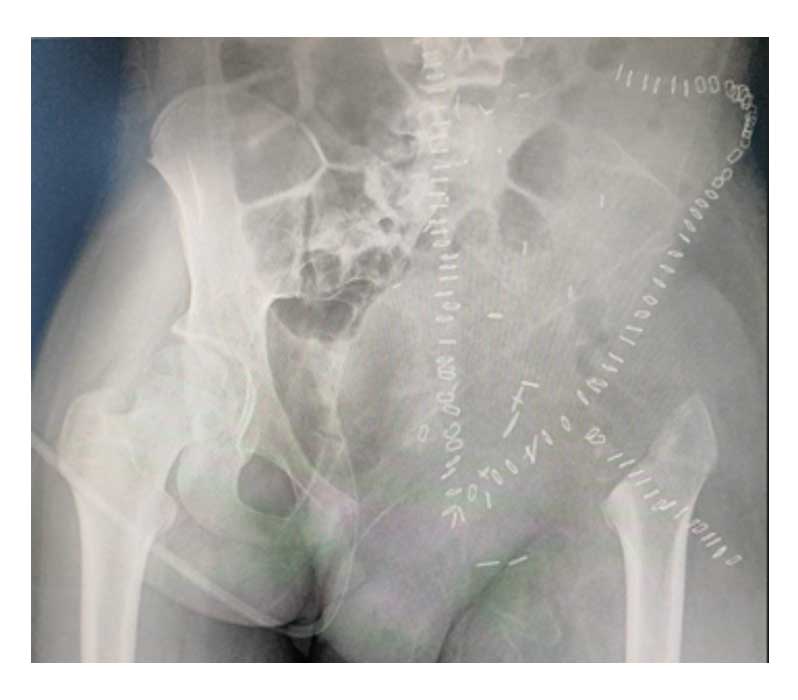

Ameliyat Sonrası: Röntgende rezeksiyon sonrası görülmekte.